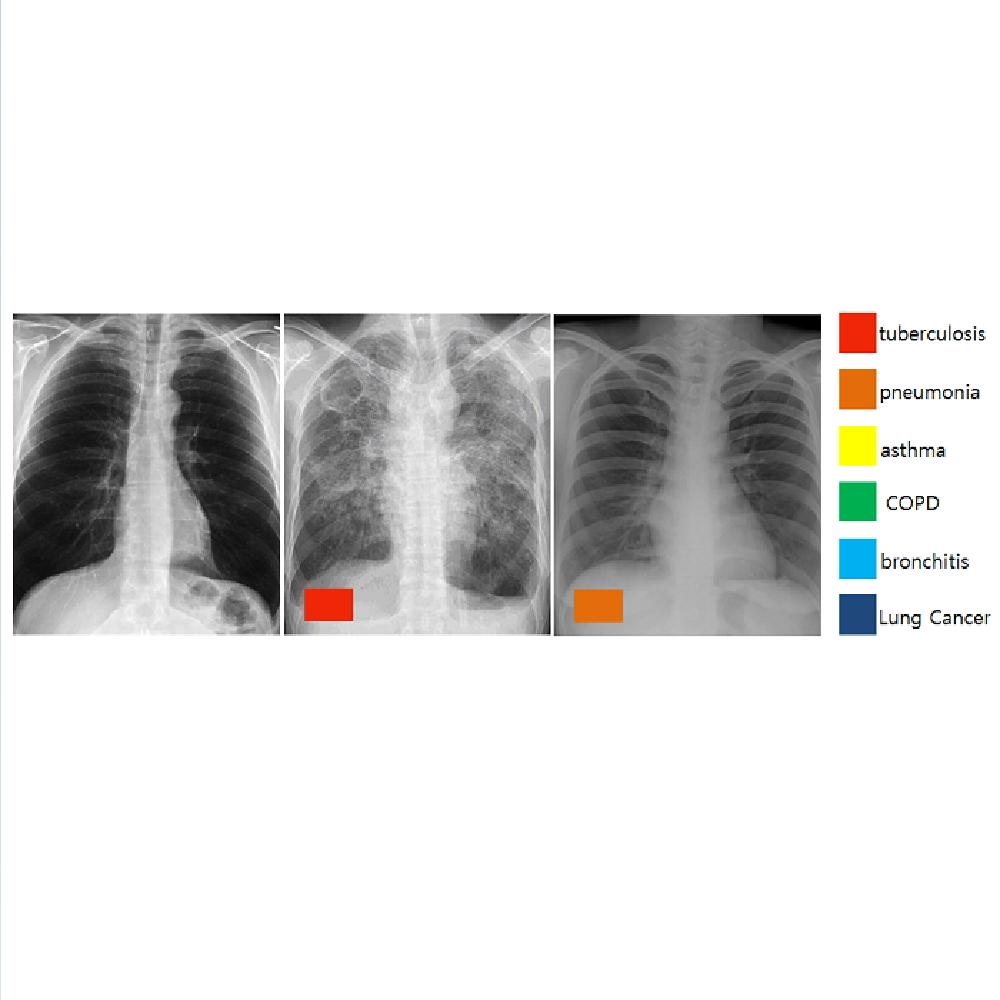

Digital X-ray Radiography Auto decipher

Chest X-Ray

Digital X-ray Radiography Auto decipher

-Based on AI, automagical diagnosis model development for error of DXR-

Need for exact examination of tuberculous (Chest X-Ray)

-Patients have not received exact tuberculous test through chest X-Ray

For tuberculous, the early diagnosis is key

-Need for exact diagnosis of tuberculous, especially where there is no Radionologist

-Prevention through Early diagnosis

Need for exact examination of tuberculous (Chest X-Ray)

70% of hospitals do not have any Radionic Technologist

Patients have not received exact tuberculous test through chest X-Ray

For tuberculous, the early diagnosis is key